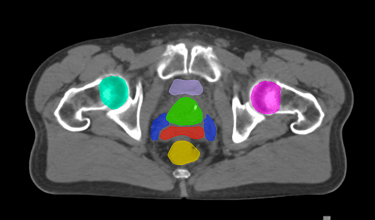

The DAM Contour features a comprehensive collection of OARs and CTVs that are ready for immediate use, without the need for manual creation of atlases or manual adjustment of data. This product includes all standard OAR and CTV structures (over 117 in total).

The Pelvis lymph node region encompasses lymph nodes that include the obturator lymph nodes, internal and external iliac lymph nodes (limited anteriorly at the level of the femoral heads), and extends up to the common iliac lymph nodes, covering the L5/S1 region.

Pelvis